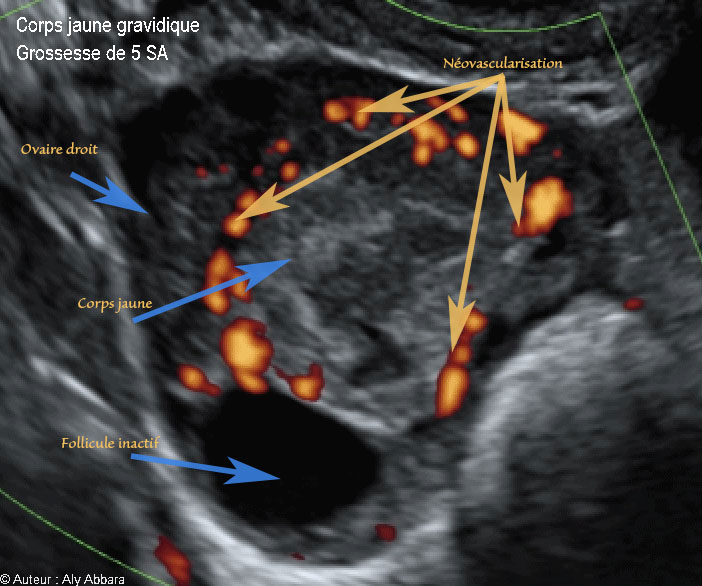

Corps jaune gravidique dans l'ovaire droit - Doppler Energie - جسم أصفر حملي في المبيض الأيمن -  5 SA

• Vidéo et image animée échographiques montrant un corps jaune gravidique, dans l'ovaire, chez une femme enceinte de 5 SA :